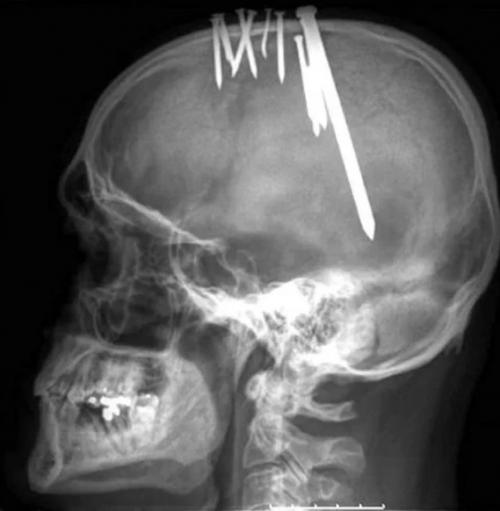

В прошлом у пациента были эпизоды депрессии, расстройства личности и попытки преднамеренного самоповреждения. Однако в последнее время он чувствовал себя хорошо. Мужчина регулярно обрабатывал раны антисептиком и скрывал их под головным убором. За два дня до того, как обратиться в больницу, он забил гвоздь длиной 12, 7 см, что значительно превышало размеры предыдущих гвоздей

.